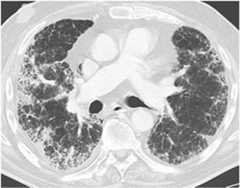

Drug-induced lung disease with am NSIP pattern. The patient has undergone chemotherapy for bladder cancer. Chest CT at the level of the right pulmonary artery at lung window. Diffuse bilateral peripheral reticular pattern, ground glass, and some consolidation.

Image: “Drug-induced lung disease” by Department of Diagnostic and Interventional Radiology, Marien Hospital, Academic Teaching Hospital, Rochusstr. 2, D- 40479, Düsseldorf, Germany. License:CC BY 4.0